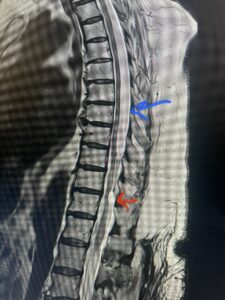

This 67-year-old female presents with progressive heaviness and numbness of the legs and difficulty ambulating. Her right leg was worse than her left. She had right greater than left hip flexor weakness. She was hyperreflexia in her lower extremities. An MRI (Fig. 1) demonstrated an intradural arachnoid cyst at T10-11 with severe spinal cord compression. She also appeared to have an arachnoid cyst above from T4-T8 with anterior displacement and compression of the spinal cord. Because of her severe myelopathy and the findings on MRI the patient underwent laminectomy for surgical decompression of cyst. Intraoperatively the focal arachnoid cyst at T10-11 appeared as a small bubble crushing the spinal cord anteriorly with scarring of the arachnoid with no CSF flow above or below.

The cyst was fenestrated and immediately CSF flow was reestablished. We performed a laminectomy at T6-7 for the upper cyst region which was observed to be more consistent with normal anatomy. We fenestrated the arachnoid. It was felt that the upper level was a secondary phenomenon as a result of CSF flow blockage. Post operatively she had an uneventful course with return of normal strength although she had some residual numbness.

Fig. 1 Sagittal T2-weighted thoracic MRI demonstrating both T10-11 focal intradural arachnoid cyst (red arrow) and larger upper thoracic cyst that appears to extend from T4-T8 (blue arrow).

Fig. 1b Axial T2-weighted thoracic MRI demonstrating spinal cord compression from T10-11 arachnoid cyst (red arrow)